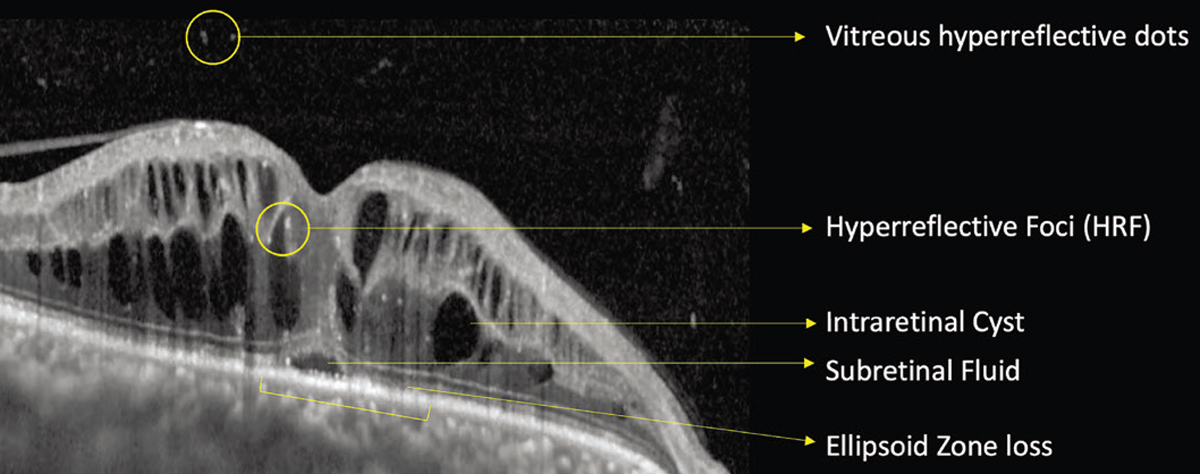

However, if the edema exceeds these elastic limits, bipolar axons snap, irreparably compromising this transmission pathway. This explains why visual acuity may not fully recover to baseline even after UME resolves.3 Features of UME associated with visual acuity include intraretinal cystoid spaces and subretinal fluid (Figure 1). Larger cysts have a greater impact.4

| Figure 1. Optical coherence tomography showing uveitic macular edema with various anatomical parameters that are useful biomarkers, including vitreous hyperreflective dots, hyperreflective foci, intraretinal cysts, subretinal fluid and ellipsoid zone loss. |